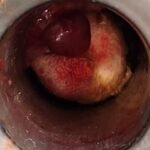

LASER LIAS FOR ANAL FISSURES AND BANDING OF HEMORRHOIDS